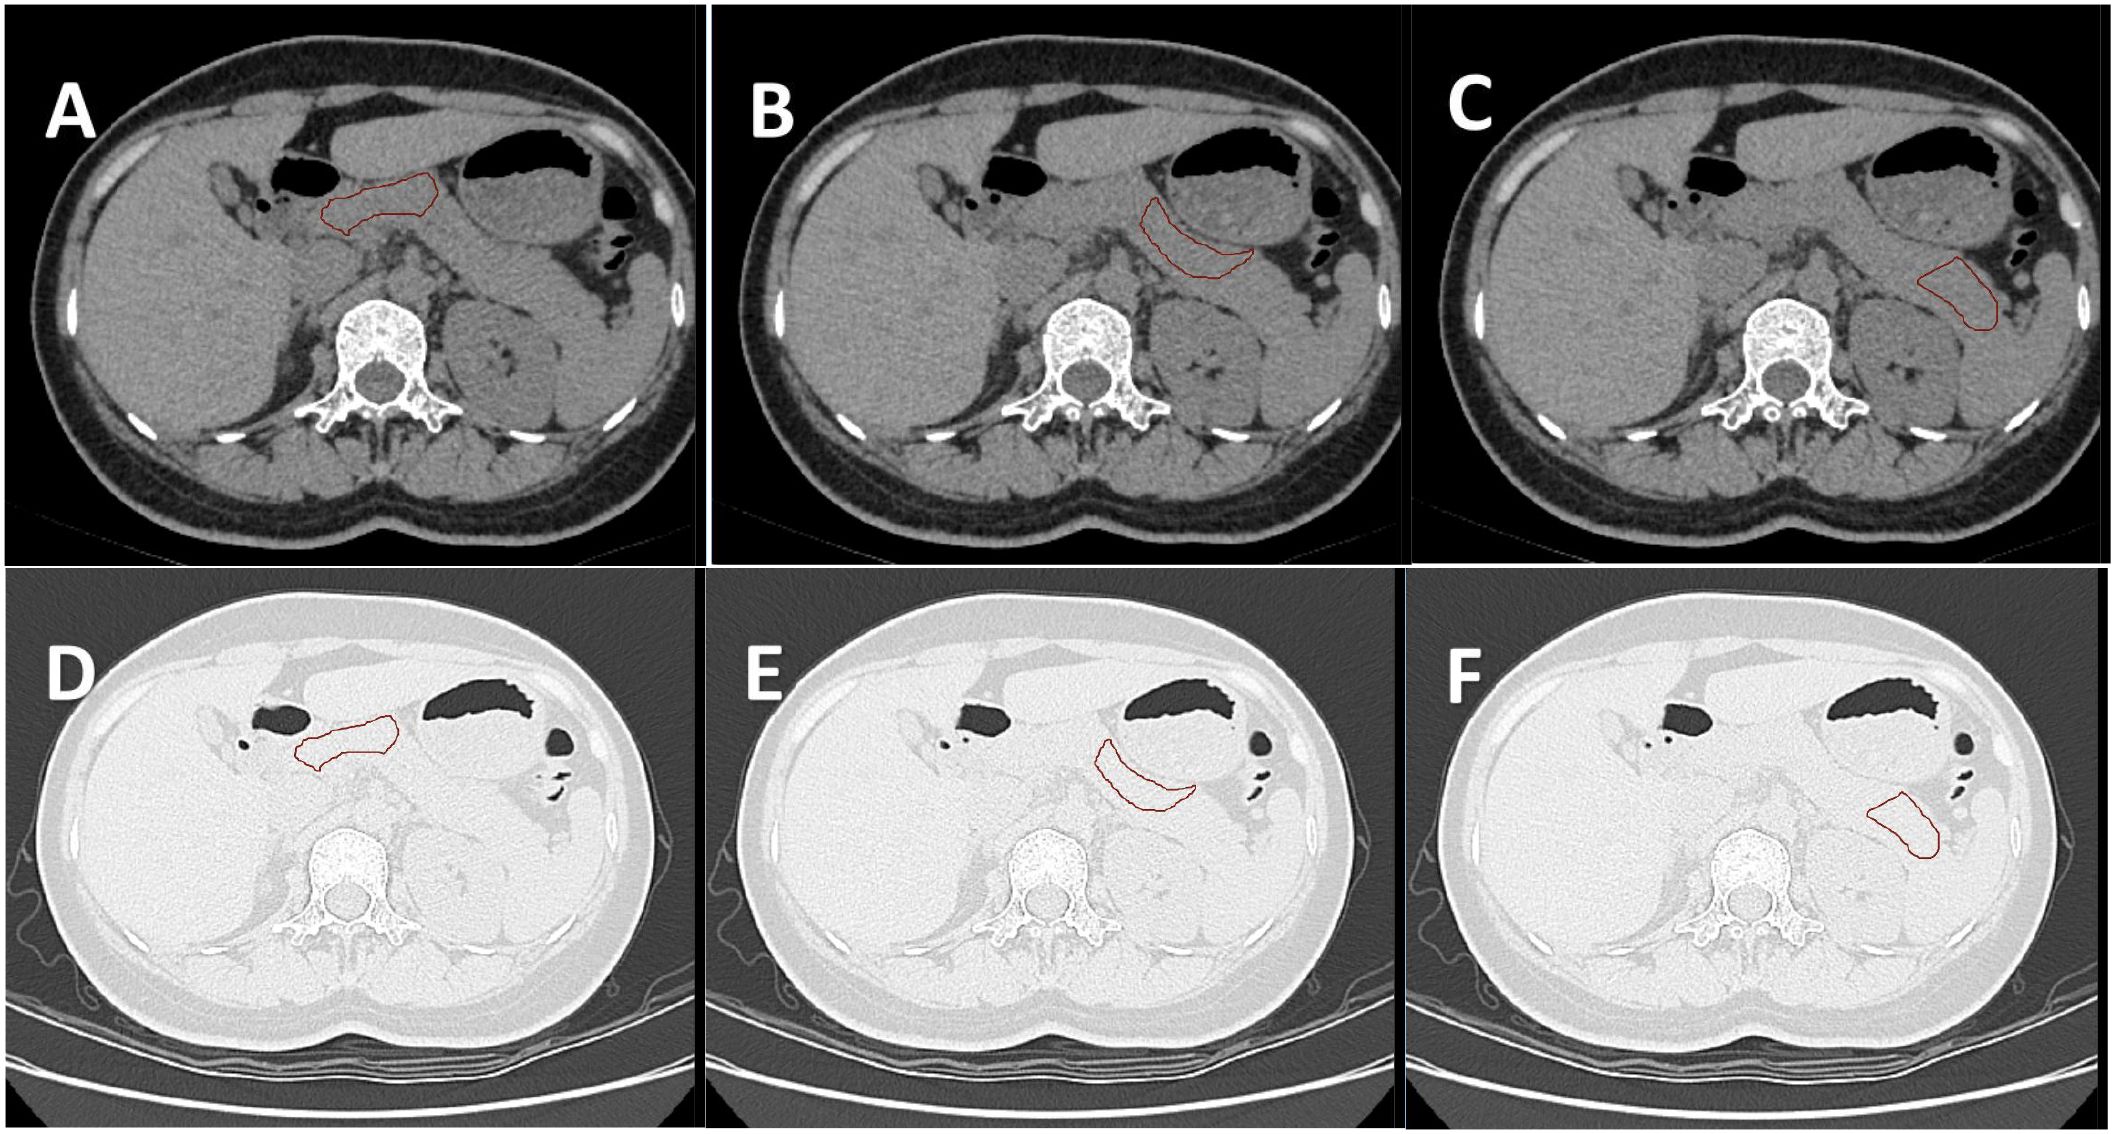

Image data processing specifically included the following steps: (1) Two-dimensional segmentation of Region of interest (ROI): Six samples of pancreatic head-neck, pancreatic neck-body, and pancreatic body-tail were delineated in the lung window and soft tissue window, respectively (12, 13) (Figure 2). The six obtained samples were respectively used as independent samples for feature extraction.

Figure 2. (A–C) show the ROI of the pancreatic head-neck, neck-body, and body-tail delineated by the soft tissue window of the same subject, respectively. (D–F) are the ROI of the lung window registered by the automatic registration function of the software, respectively. A total of six samples were obtained for one subject.